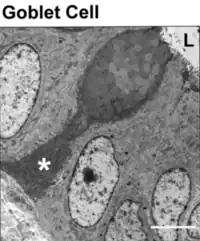

Caliciforme (asterisco) con granos de mucina en su mitad superior. Microscopio electrónico de transmisión.

Célula caliciforme